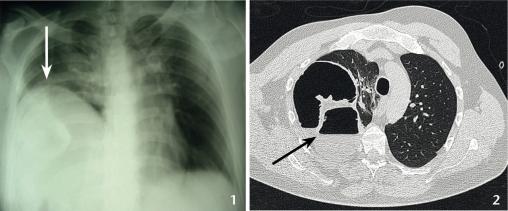

La radiographie de thorax (fig. 1) met en évidence une forte « ascension diaphramatique » à droite. Le scanner sans injection (fig. 2) montre des anses grêles dans l’hémithorax droit avec signes d’occlusion sans perforation.